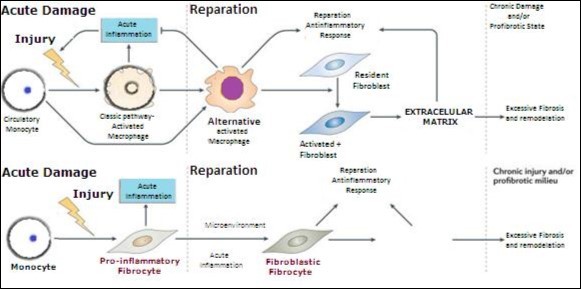

Inflammation and Endothelial dysfunction, participate directly in the activation of fibroblasts responsible for excess remodeling and fibrosis of the extracellular matrix. figure 5

Figure 5.Direct and indirect way of activation of fibroblasts by monocyte-macrophages.